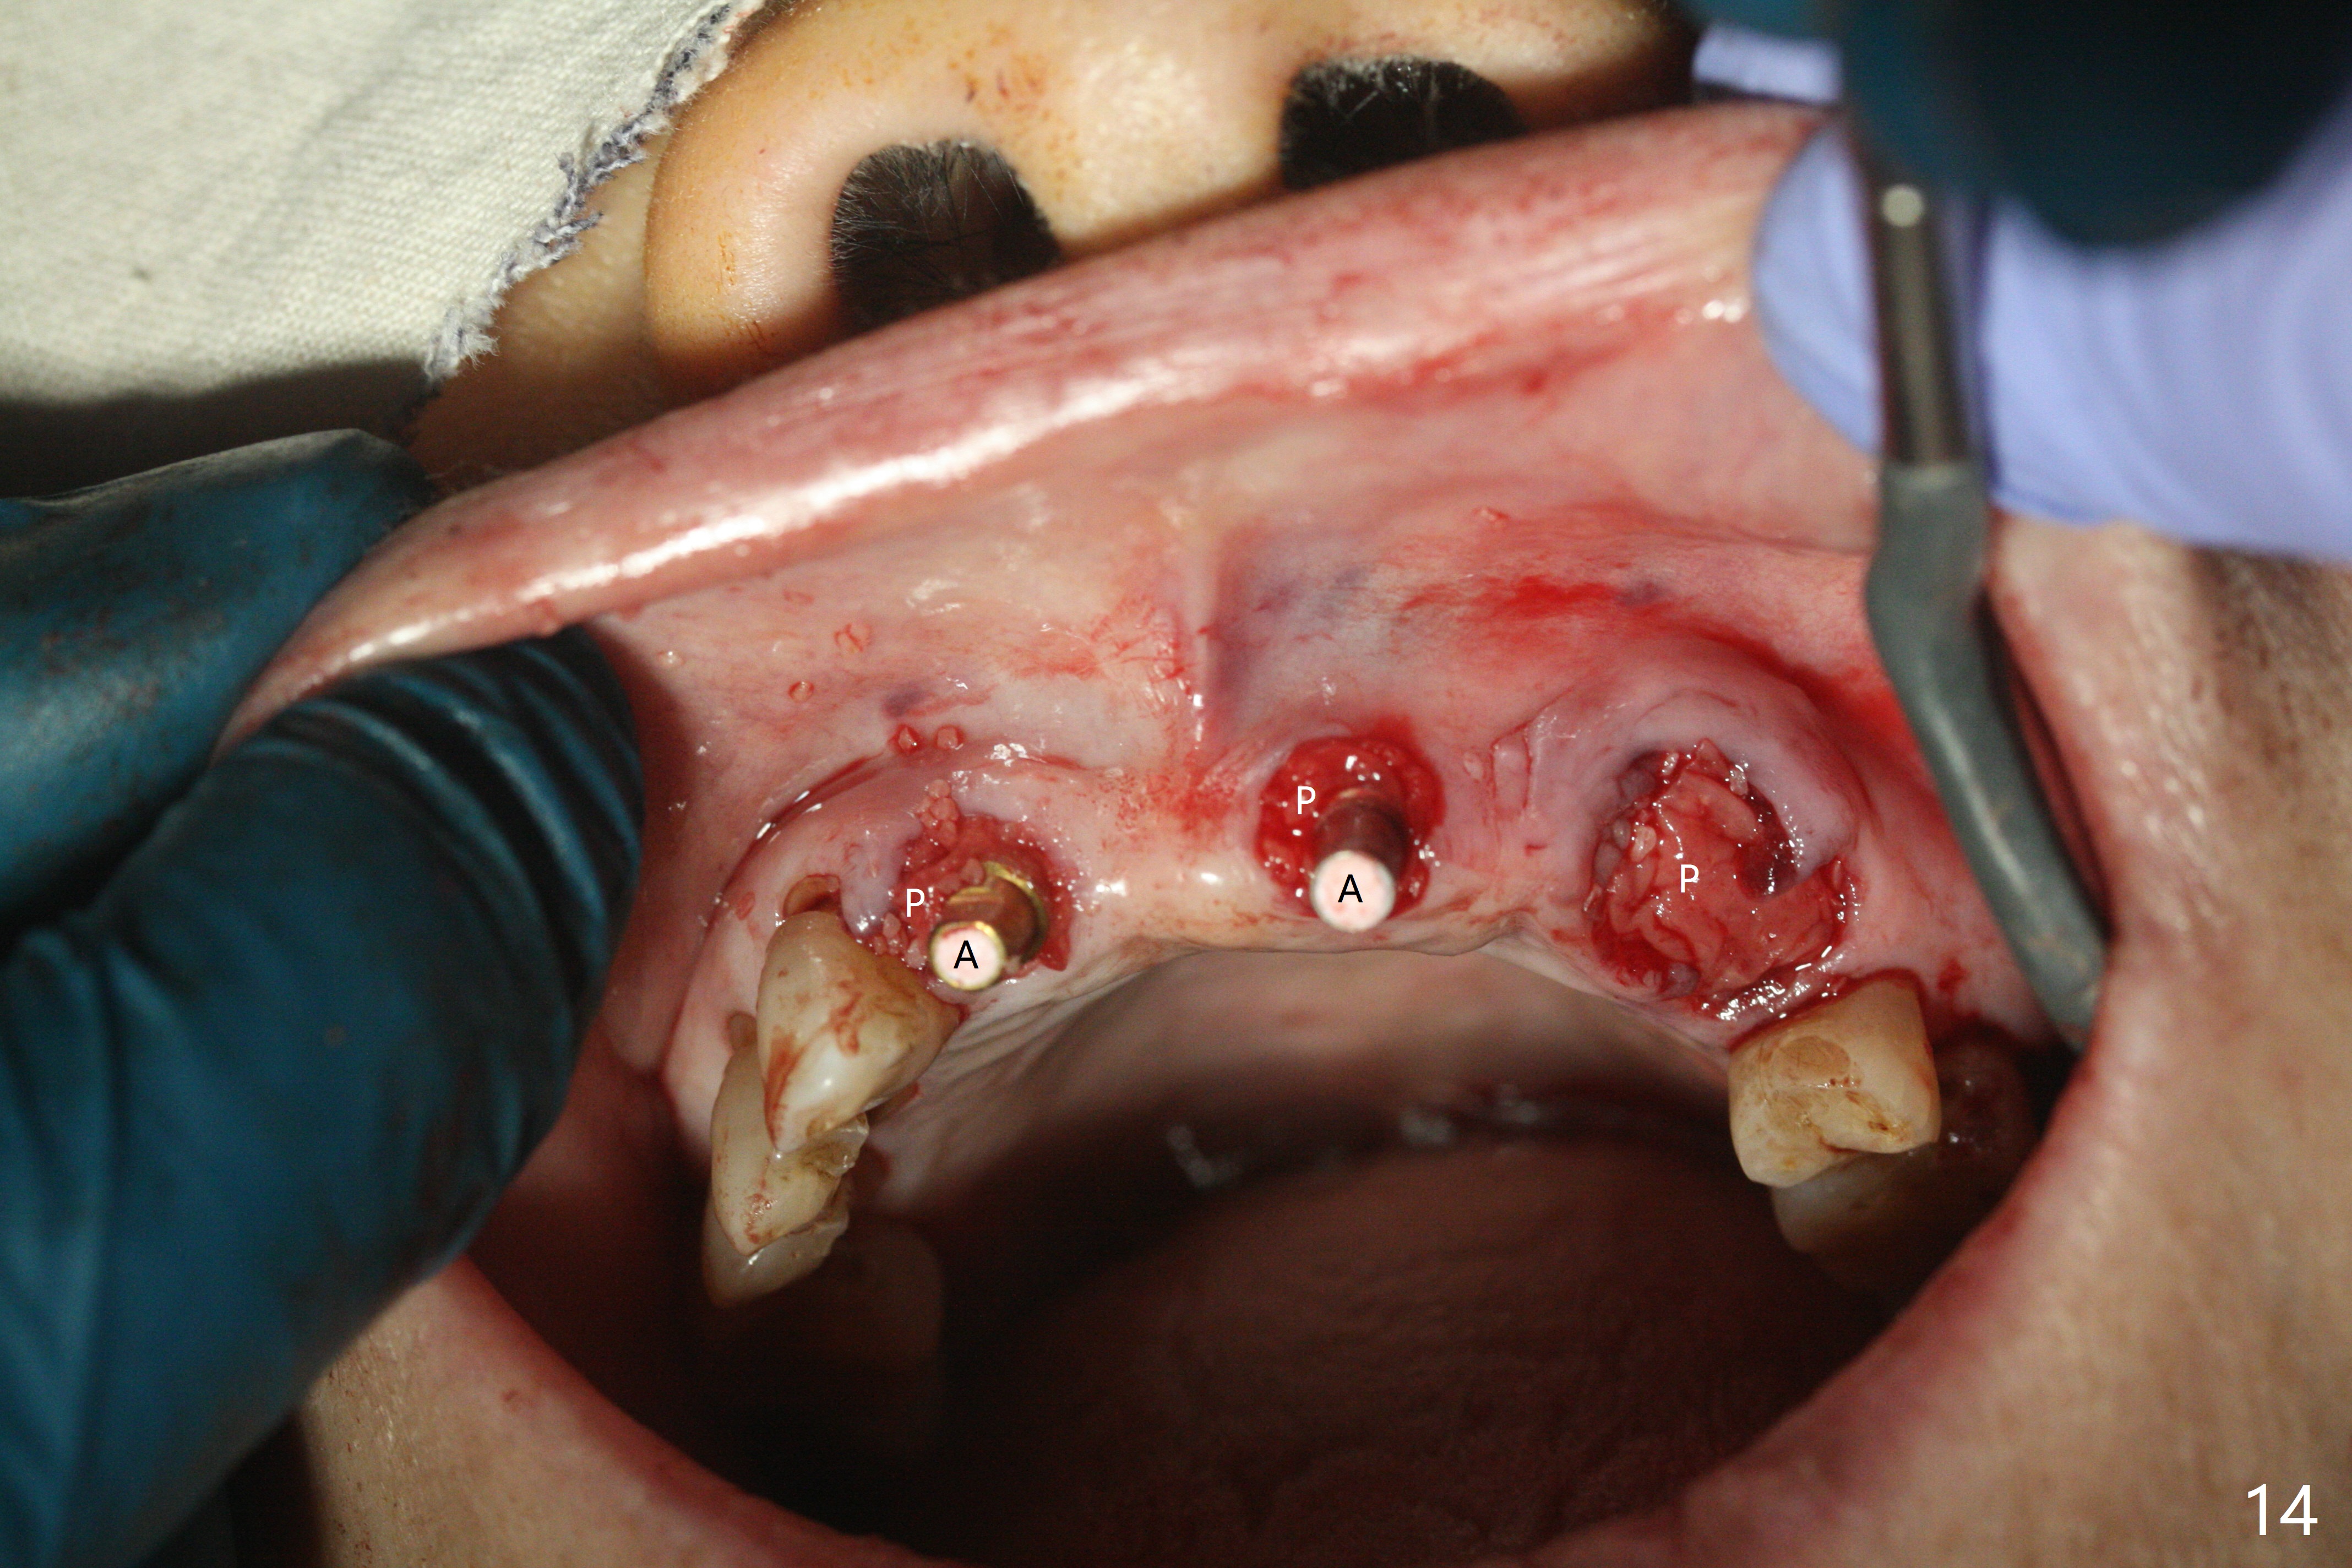

今天下午进入治疗室,粘性骨粉已制备:上清液来自红管(含促凝剂),离心3分钟(图一);再离心10分钟上清液就转变PRF,压制后,使用前剪成三块(图二:黑线),其中两块punch一个洞(图二:圆圈),插入7,9号牙基台固定;大块覆盖11/12号牙牙槽窝(图十四)。7,9,11,12号牙必须拔除(图三),然后在7,9,12种植。由于缺失左下磨牙,前牙垂直距离减少(图四)。完成9号牙位钻洞后,利用fixture mount(图五:M)植入植体,并留在原位固定导板(图六),然后7号牙种植,也留下fixture mount(图六:7,9),最后完成12号牙植入,但是后者扭力低,放置愈合螺帽(图九),而7,9号牙位放置修复基台(图七,八(使用5.5毫米profile drill后),好像基台没有完全就位。7号牙位更换基台似乎没帮助(图十),9号牙位再次放置同一个基台临床上仿佛有改变(比较图八与十二)。放置粘性骨粉后(图十一至十三),牙槽窝口覆盖PRF膜(图十四:P(A:基台)),最后使用树脂敷料固定骨粉和膜(图十五,六),基台帮助敷料固位,没有咬合干扰(图十七:*)。树脂敷料部分解决美观问题,一个月后撤除,如果植体仍有稳定性,可能制作7-10临时牙桥,可能部分维持或者恢复牙龈外形。术后一周病人主诉后面植牙和鼻底疼痛,11号牙根尖牙龈充血(图十八),轻度触痛,可能与术中尚未完全清创有关(图十九(术前CT 3D图像))。再服用Amoxicillin一周,症状好转,鼻底轻度触痛(图二十)。术后1.5月没有任何不适,撤除树脂敷料,7号牙基台(袖)显得太长,换一个短的(4.5x4(5)(图十,十一)->4x4(3)毫米)毫米),植骨好像愈合正常(图二十一:*)。7号牙换了短的基台,9号牙基台高度调整后,与对合牙有足够空间做临时牙桥,最好8,10号牙位牙龈应该凹陷(图二十二:*),有pontic外形。另外9号牙基台颊侧牙龈边缘有所修整,临时牙桥准备。先做7-10临时牙桥,理想临时牙桥pontic处树脂应该多些(图二十三:白线)压迫牙龈形成凹陷。11,12号牙牙槽窝在树脂(Bosworth)敷料下也正常愈合(图二十四)。